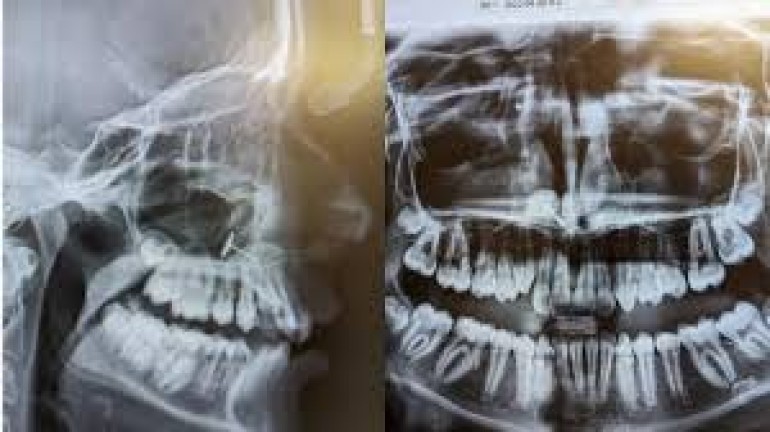

वॉशिंगटन,। अमेरिका के वॉशिंगटन स्टेट में महिला अपनी बेटी को साधारण डेंटल चेकअप विजिट के लिए ले गई, लेकिन जब एक्स-रे रिपोर्ट सामने आई तो सभी हैरान रह गए। फिर जब यह बात बेटी को मालूम चली तो उसने राज से पर्दा उठा दिया।जानकारी अनुसार 13 साल की बच्ची को ब्रेसेज लगाने से पहले जब डॉक्टर ने उसके दांतों का एक्स-रे निकाला, तो तस्वीर में ऐसा कुछ नजर आया, जिसे देख सभी दंग रह गए। मीडिया रिपोर्ट के मुताबिक, एक्स-रे स्क्रीन पर साफ दिख रहा था कि बच्ची की साइनस में धातु का एक छोटा टुकड़ा फंसा हुआ है।

मां के लिए यह किसी बड़े रहस्य से कम न था, लेकिन जब बेटी से बात की गई तो वह तुरंत समझ गई कि यह वहां कैसे पहुंचा। दरअसल करीब छह माह पहले बेटी ने मां से नाक छिदवाने की जिद की थी। मां ने मना कर दिया कि 16 साल की उम्र से पहले नोज पियर्सिंग नहीं होगी। लेकिन बच्ची, जिसे गंभीर एडीएचडी की समस्या है और इम्पल्स कंट्रोल कम था, ने खुद ही कान छिदवाने वाली इयररिंग से नाक में छेद करने की कोशिश की। उसी दौरान धातु का छोटा हिस्सा नाक से होते हुए साइनस में फंस गया।